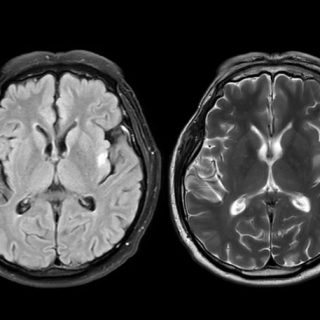

This insight could eventually help doctors diagnose Parkinson’s earlier. Today, identifying the disease often takes years and usually involves a long series of clinical evaluations. A simple smell based test could offer a faster, cheaper and non invasive alternative. Loss of the sense of smell is already known to be…